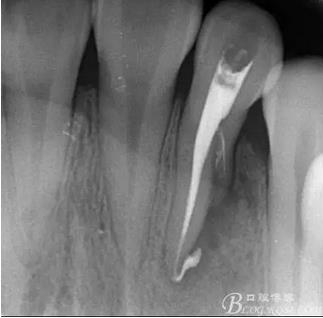

(6)復診:原暫封材料再位,牙周無明顯異常與不適,常規(guī)清潔根管,H銼清除根管內(nèi)維他,次氯酸鈉終末消毒,干燥根管,單尖測壓發(fā)充填根管,術(shù)后拍片到位。